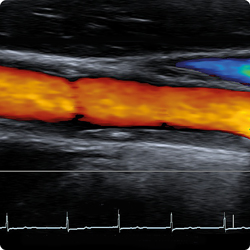

Die Duplexsonographie der hirnzuführenden Gefässe erlaubt nicht nur die Stenosegraduierung, aber auch mittels B-Modus Rückschlüsse auf die Plaquestabilität.